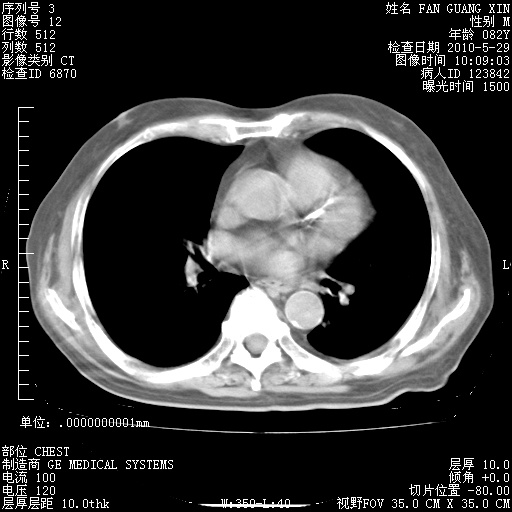

再治疗10天后的肺部CT 纵膈窗

阅读此次胸部CT,肺间质渗出性改变较入院时有吸收。目前从体温、白细胞、中性分叶明显增高,肯定存在细菌感染(发生医院感染哦,若无消化道及泌尿系统等感染的依据,肺部感染可能大)。若你院头孢哌酮舒巴坦钠耐药率较高,同意你的方案,若48小时体温仍高,可考虑使用碳青霉稀类抗菌药物,同时可予超声雾化、注意滴数时加大液体量。白蛋白33.30g/L较低哦,需加强营养等支持治疗。